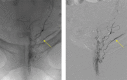

Emborrhoid: Rectal Artery Embolization for Hemorrhoid Disease

- Vidal V, Louis G, Bartoli J M, Sielezneff I. Embolization of the hemorrhoidal arteries (the emborrhoid technique): a new concept and challenge for interventional radiology. Diagn Interv Imaging. 2014;95(03):307–315. - PubMed

- Tradi F, Louis G, Giorgi R. Embolization of the superior rectal arteries for hemorrhoidal disease: prospective results in 25 patients. J Vasc Interv Radiol. 2018;29(06):884–8920. - PubMed